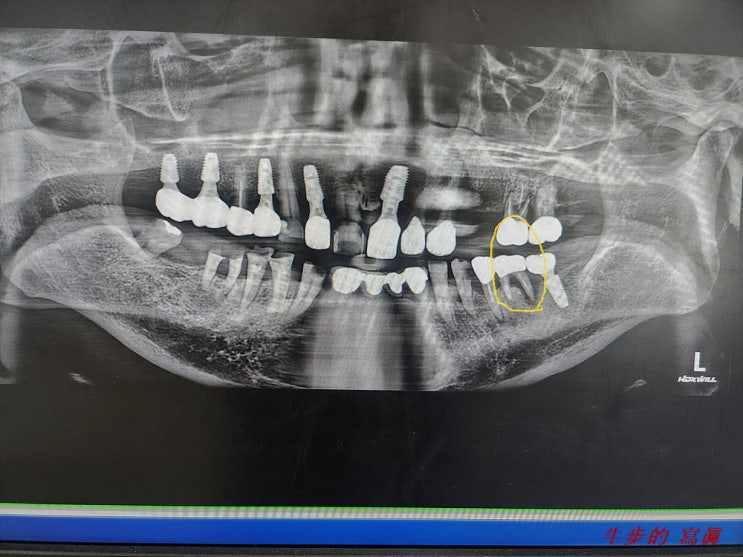

[My Job.] 하악 소구치 즉발즉립...

3월의 첫 진료일인 4일 오전... 한분의 新患께서 나를 찾아주셨다. 파노라마 사진을 보니..... 여러곳의 치...